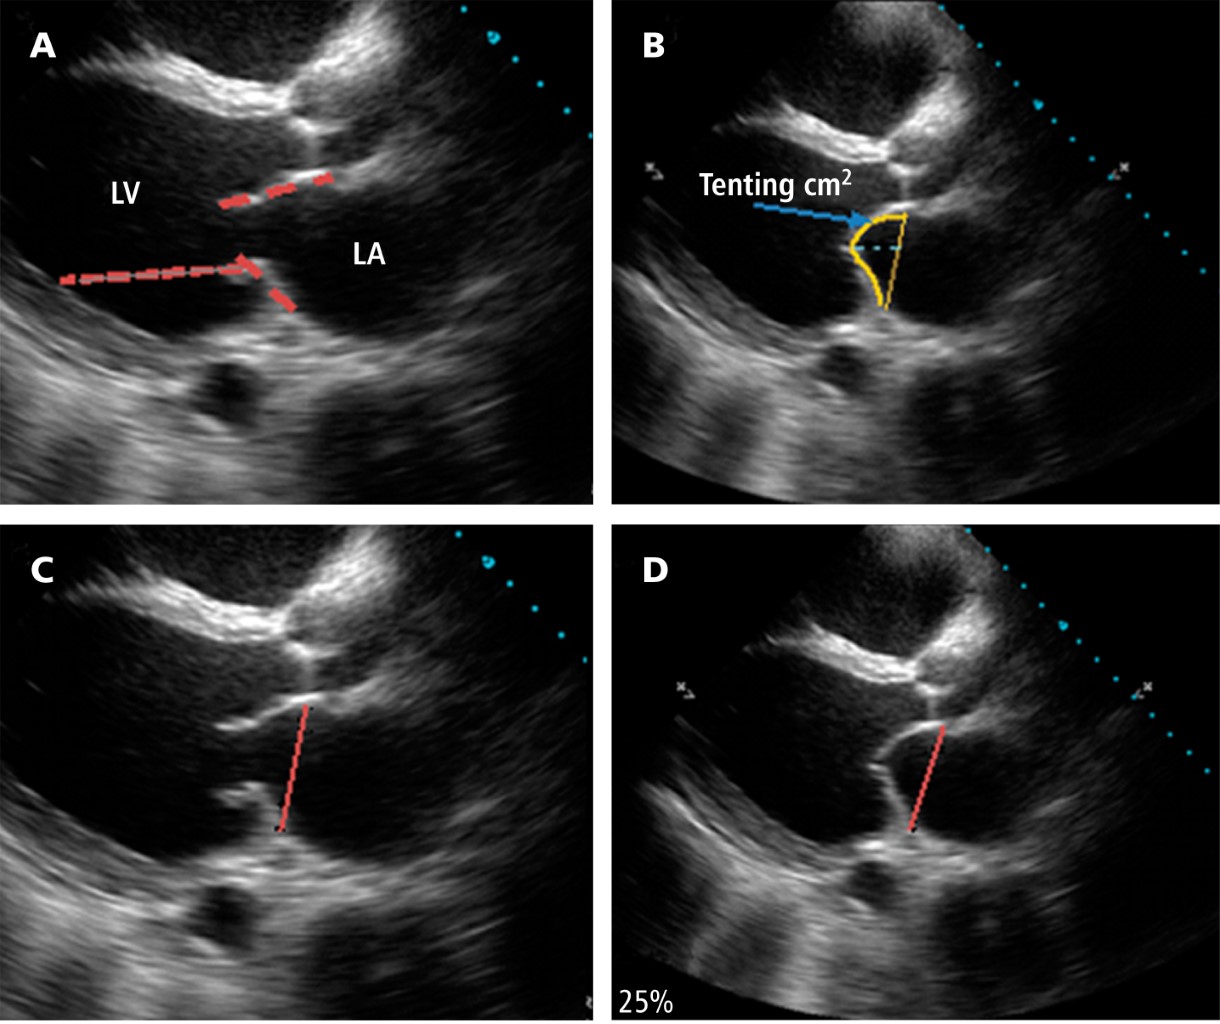

Figura 1

Figura 2

Figura 3

Figura 4